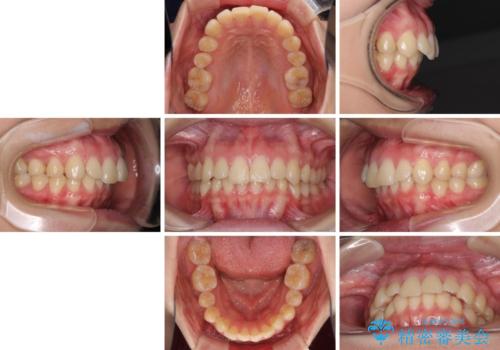

左右ともに下顎に対して上顎歯列が前方位にある上顎前突であったので、上顎歯列全体を後方に移動させることで上下咬み合わせを改善し、その上で抜歯矯正により口元の突出感を改善させていきました。

- 口元の突出感改善を希望して来院された患者様です。

口元を積極的に引っ込めるために、上下左右の小臼歯計4本を抜歯することとしました。

咬み合わせが深いため、咬み合わせの高さを向上させながら口元を下げることとしました。